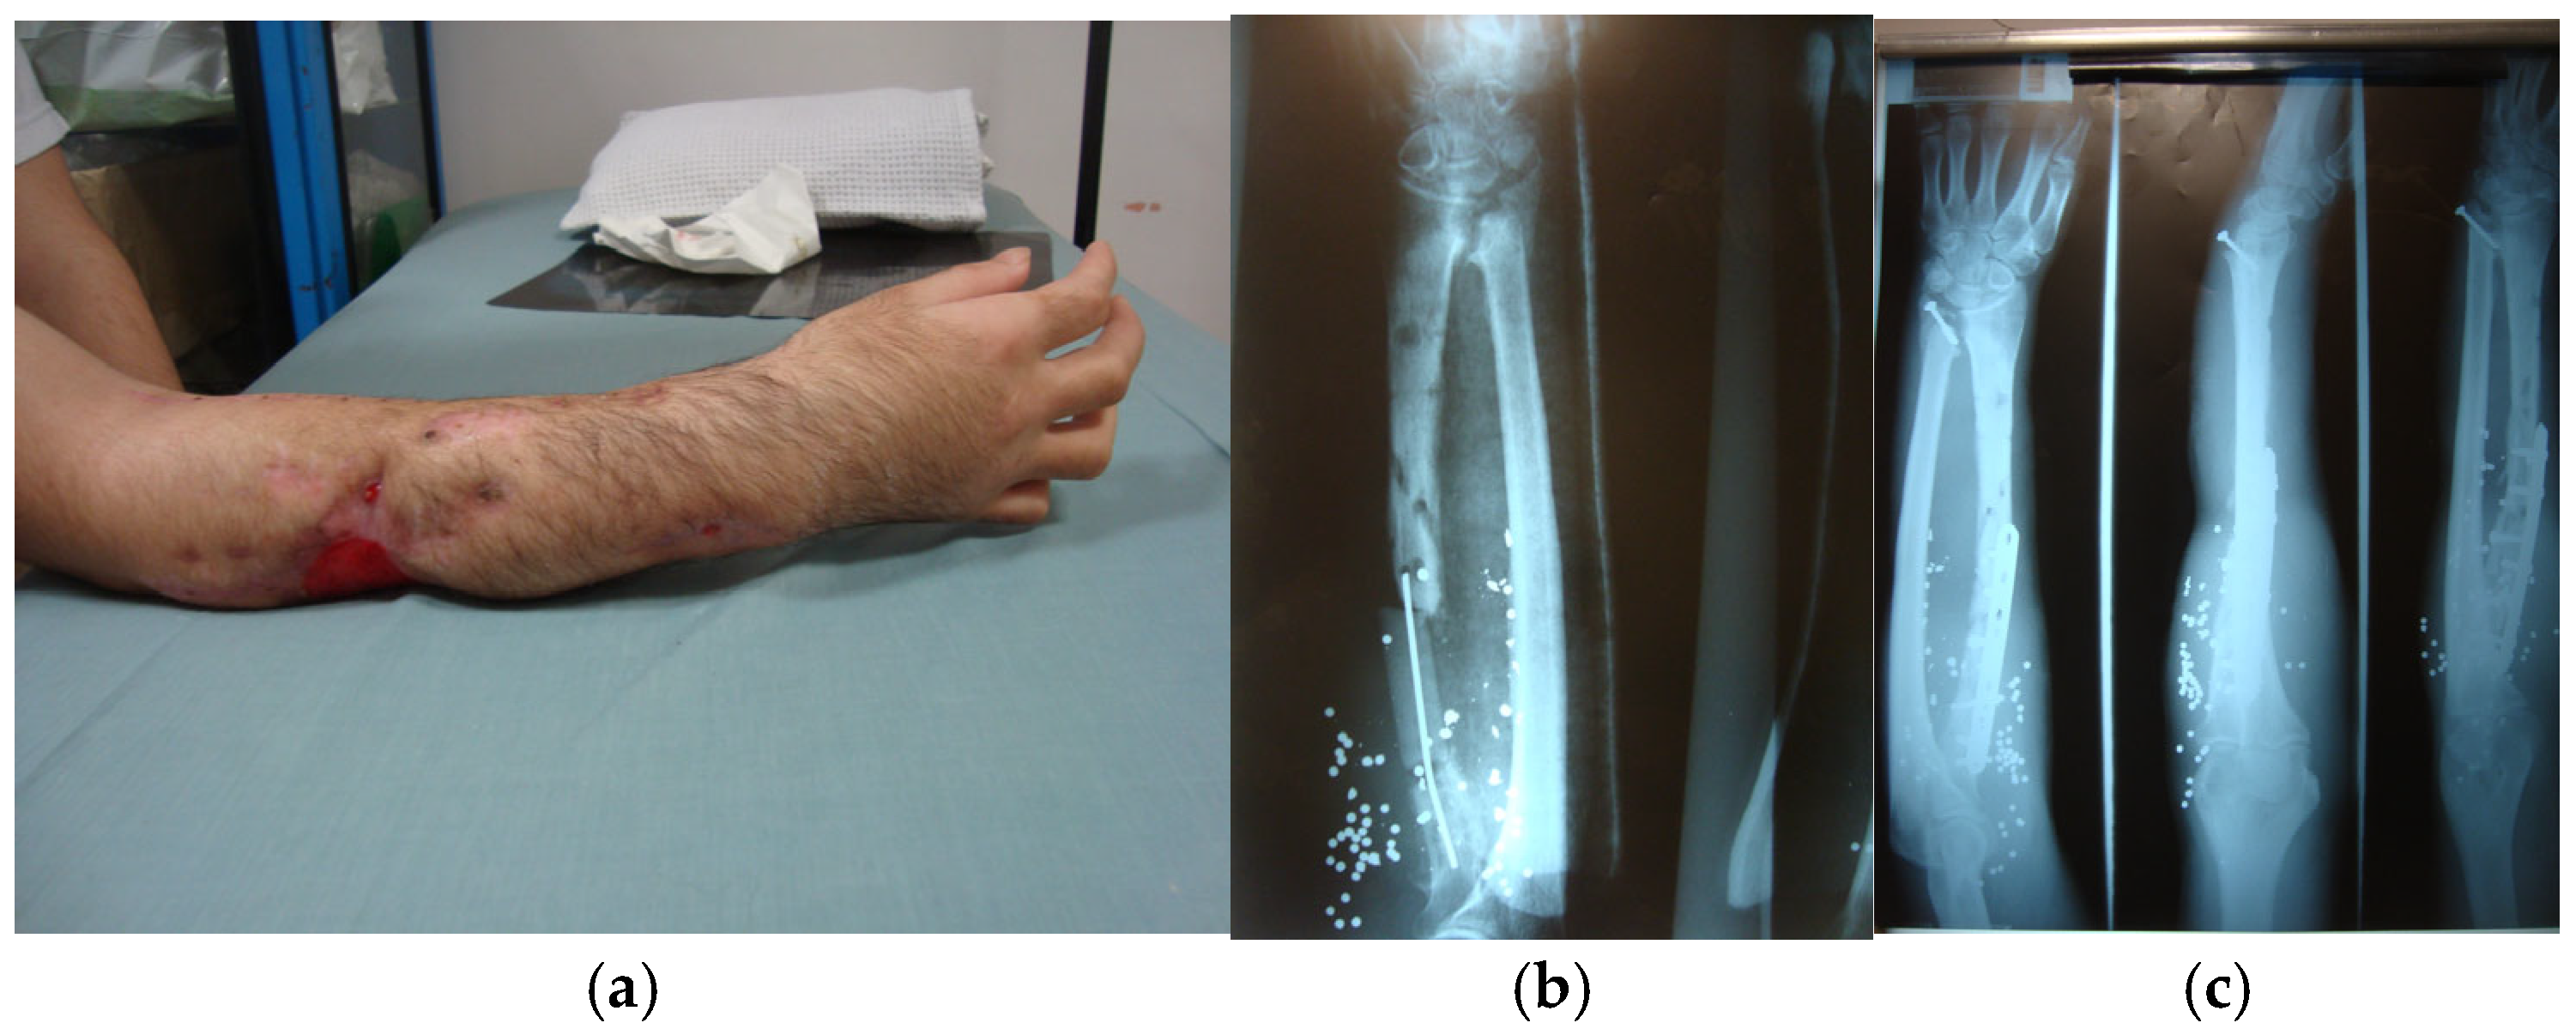

- Shin, E.H.; Sabino, J.M.; Nanos, G.P., III; Valerio, I.L. Ballistic trauma: Lessons learned from Iraq and Afghanistan. Semin. Plast. Surg. 2015, 29, 10–19. [Google Scholar] [CrossRef]

- Adams, M.H.; Gaviria, M.; Sabbag, C.M. Military ballistic injuries of the upper extremity. Hand Clin. 2025, 41, 269–280. [Google Scholar] [CrossRef] [PubMed]

- Tarkunde, Y.R.; Clohisy, C.J.; Calfee, R.P.; Halverson, S.J.; Wall, L.B. Firearm injuries to the wrist and hand in children and adults: An epidemiologic study. Hand 2023, 18, 575–581. [Google Scholar] [CrossRef] [PubMed]

- Lin, J.S.; Rhee, P.C. Wrist and forearm fractures from ballistic injuries. Hand Clin. 2025, 41, 313–322. [Google Scholar] [CrossRef]